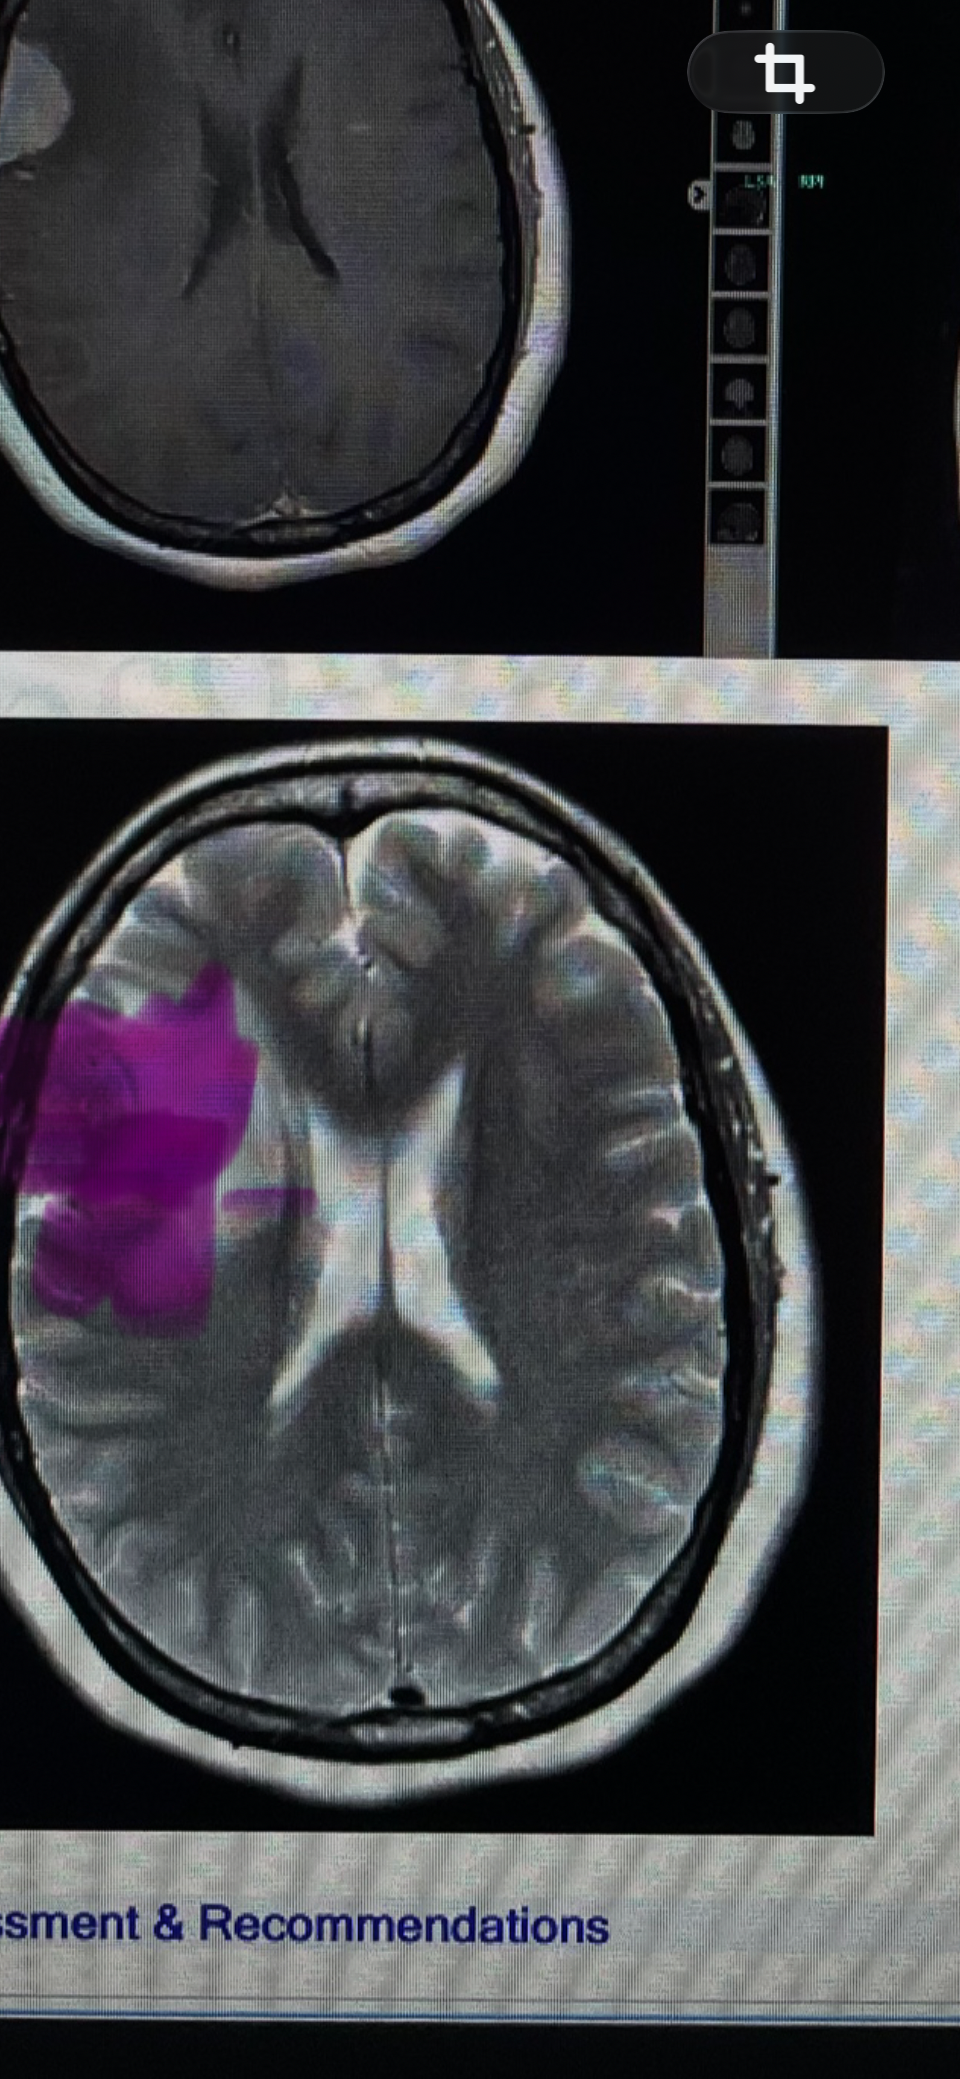

A week ago, I was diagnosed with a tumor, which led to emergency surgery. Although the operation was necessary to save my health, the medical, hospital, and recovery expenses have been overwhelming.

Hace una semana fui diagnosticada con un tumor, lo que me llevó a una cirugía de emergencia. Aunque la operación era necesaria para salvar mi salud, los gastos médicos, hospitalarios y de recuperación han sido abrumadores.